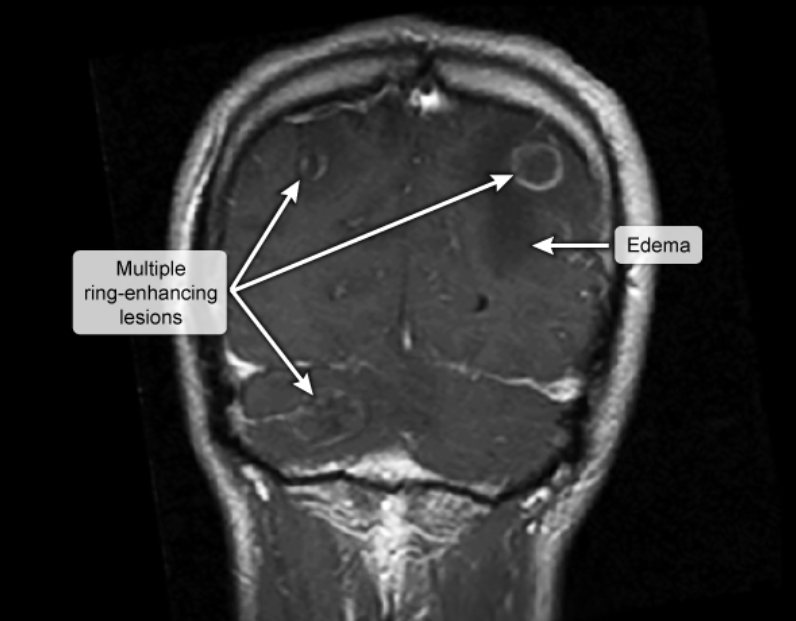

Multiple ring enhancing lesions should raise supsicion for….

Toxoplasma encephalitis

cns tuberculoma